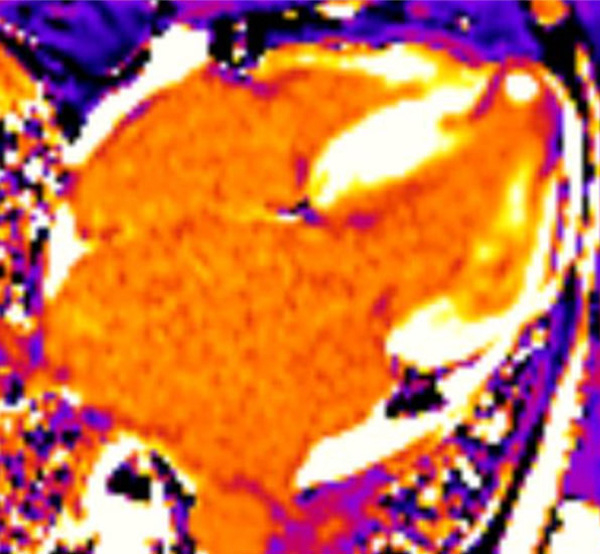

C : T1 mapping

Figure 6 : T1 natif légèrement augmenté dans le septum et la paroi latérale (fibrose)

Figure 7 : T1 post-contraste diminué à l’apex (nécrose)